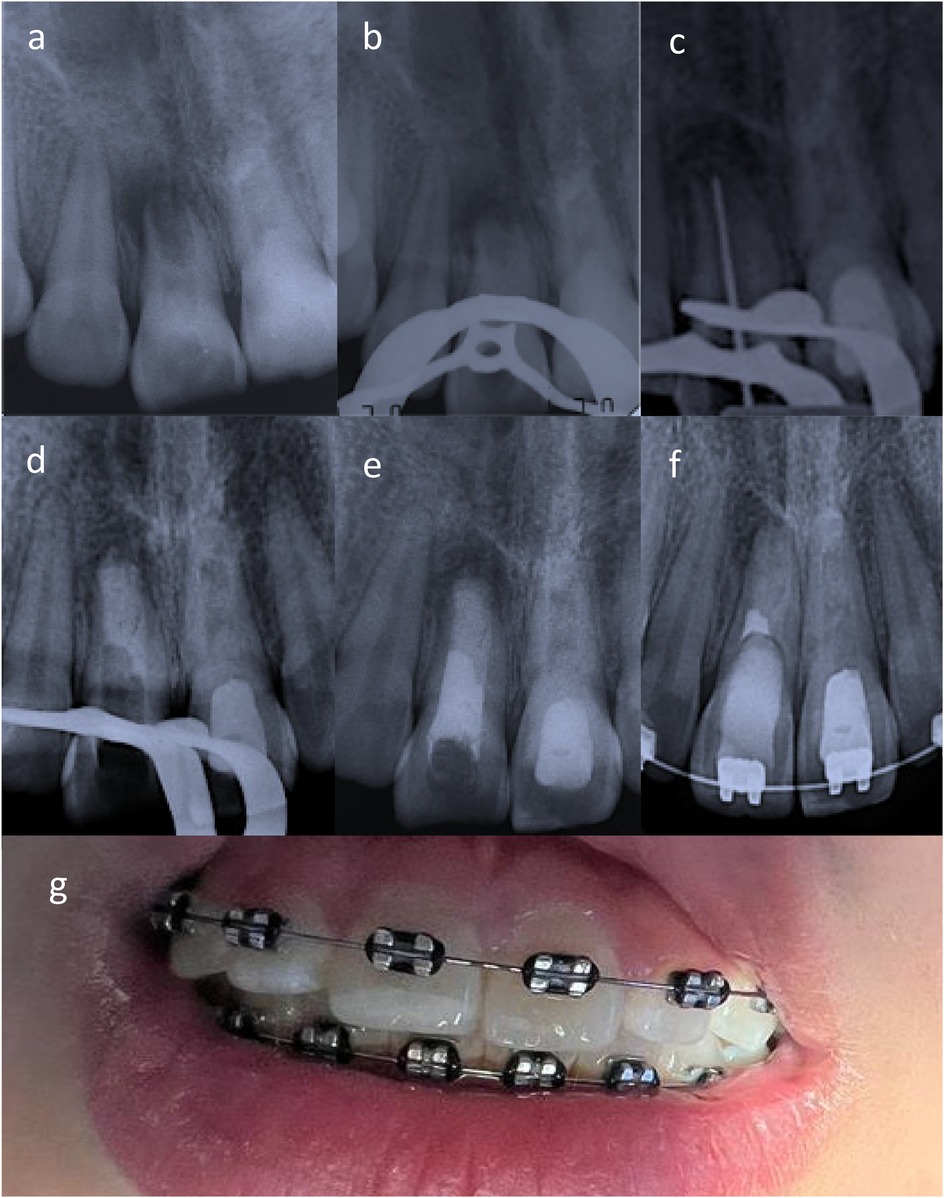

X-ray images and a photograph depict dental procedures and orthodontic work. Images a through f show various stages of dental treatment with radiographic views, highlighting differences in tooth structure and positioning. Image g displays teeth with metal braces, focusing on the orthodontic brackets and wires across the upper teeth.

Figure 2. (a) Apexification induction of tooth 1.1 was indicated given the low likelihood of apical papilla cell presence due to the surgeon's curettage. (b,c) Upon removal intracanal medication suppuration was noted. (d,e) An apical plug with bioceramic cement and thermoplastic gutta-percha (apexification) was performed. (f) Radiographically, periapical repair was evident in teeth 1.1 and 2.1. (g) Clinically, the patient was in optimal conditions, with no clinical symptoms and restored teeth undergoing orthodontic treatment.

Another month later, the decision was made to refer the patient for surgical removal of the suspected bone remnant. An oral and maxillofacial surgeon performed the surgical procedure three months later. After the surgery, an acute apical abscess (stage 3) was reported, and subsequent controls showed the persistence of the sinus tract. Clinical examination revealed continued symptomatic percussion and palpation of the vestibular fold, with an active sinus tract related to tooth 1.1. The infection was controlled with 5.25% NaOCl irrigation and intracanal medication with calcium hydroxide paste (UltraCal XS, Ultradent Products, Inc., South Jordan, UT, USA). Given the likely absence of apical papilla cells due to the surgeon's curettage, apexification was initiated (Figure 2a).

Two months later, the patient was asymptomatic, and no sinus tract was observed; however, upon removing the provisional restoration and intracanal medication for tooth 1.1, intracanal suppuration was noted. The canal was abundantly irrigated with 5.25% NaOCl and medicated with calcium hydroxide and propylene glycol paste (Figures 2b,c).

A two-month control was postponed due to the COVID-19 pandemic. After 22 months, the patient returned with an active sinus tract and intracanal suppuration in tooth 1.1. The canal was disinfected with 5.25% NaOCl, and a bi-antibiotic paste (ciprofloxacin and metronidazole 1:1 in propylene glycol) was placed and maintained for three months.

The patient was asymptomatic three years after the initial visit, with no sinus tract or signs of infection (intracanal suppuration). An apical plug with bioceramic cement (Biodentine, Septodont, France) and thermoplastic gutta-percha (apexification) was completed (Figures 2d,e). Three weeks later, the definitive coronal restoration was placed.

Two months later, the patient remained asymptomatic. Clinical and radiographic examination revealed functional, asymptomatic teeth undergoing orthodontic treatment, with periapical healing evident in 1.1 and 2.1 (Figures 2f,g).